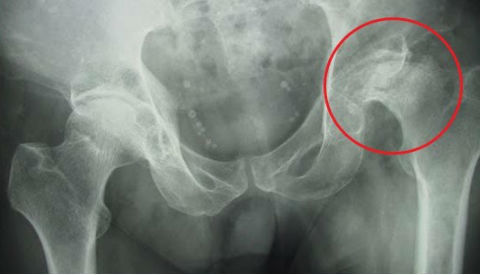

| Khối u kích cỡ lớn phá huỷ ổ cối và xâm lấn cả vào ổ bụng |

Sau khám, các bác sĩ BV K định có một khối u ở vùng ổ cối xương chậu, phá huỷ hoàn toàn ổ cối và phát triển vào ổ bụng bệnh nhân với kích cỡ khoảng 10cm, là u tế bào khổng lồ.